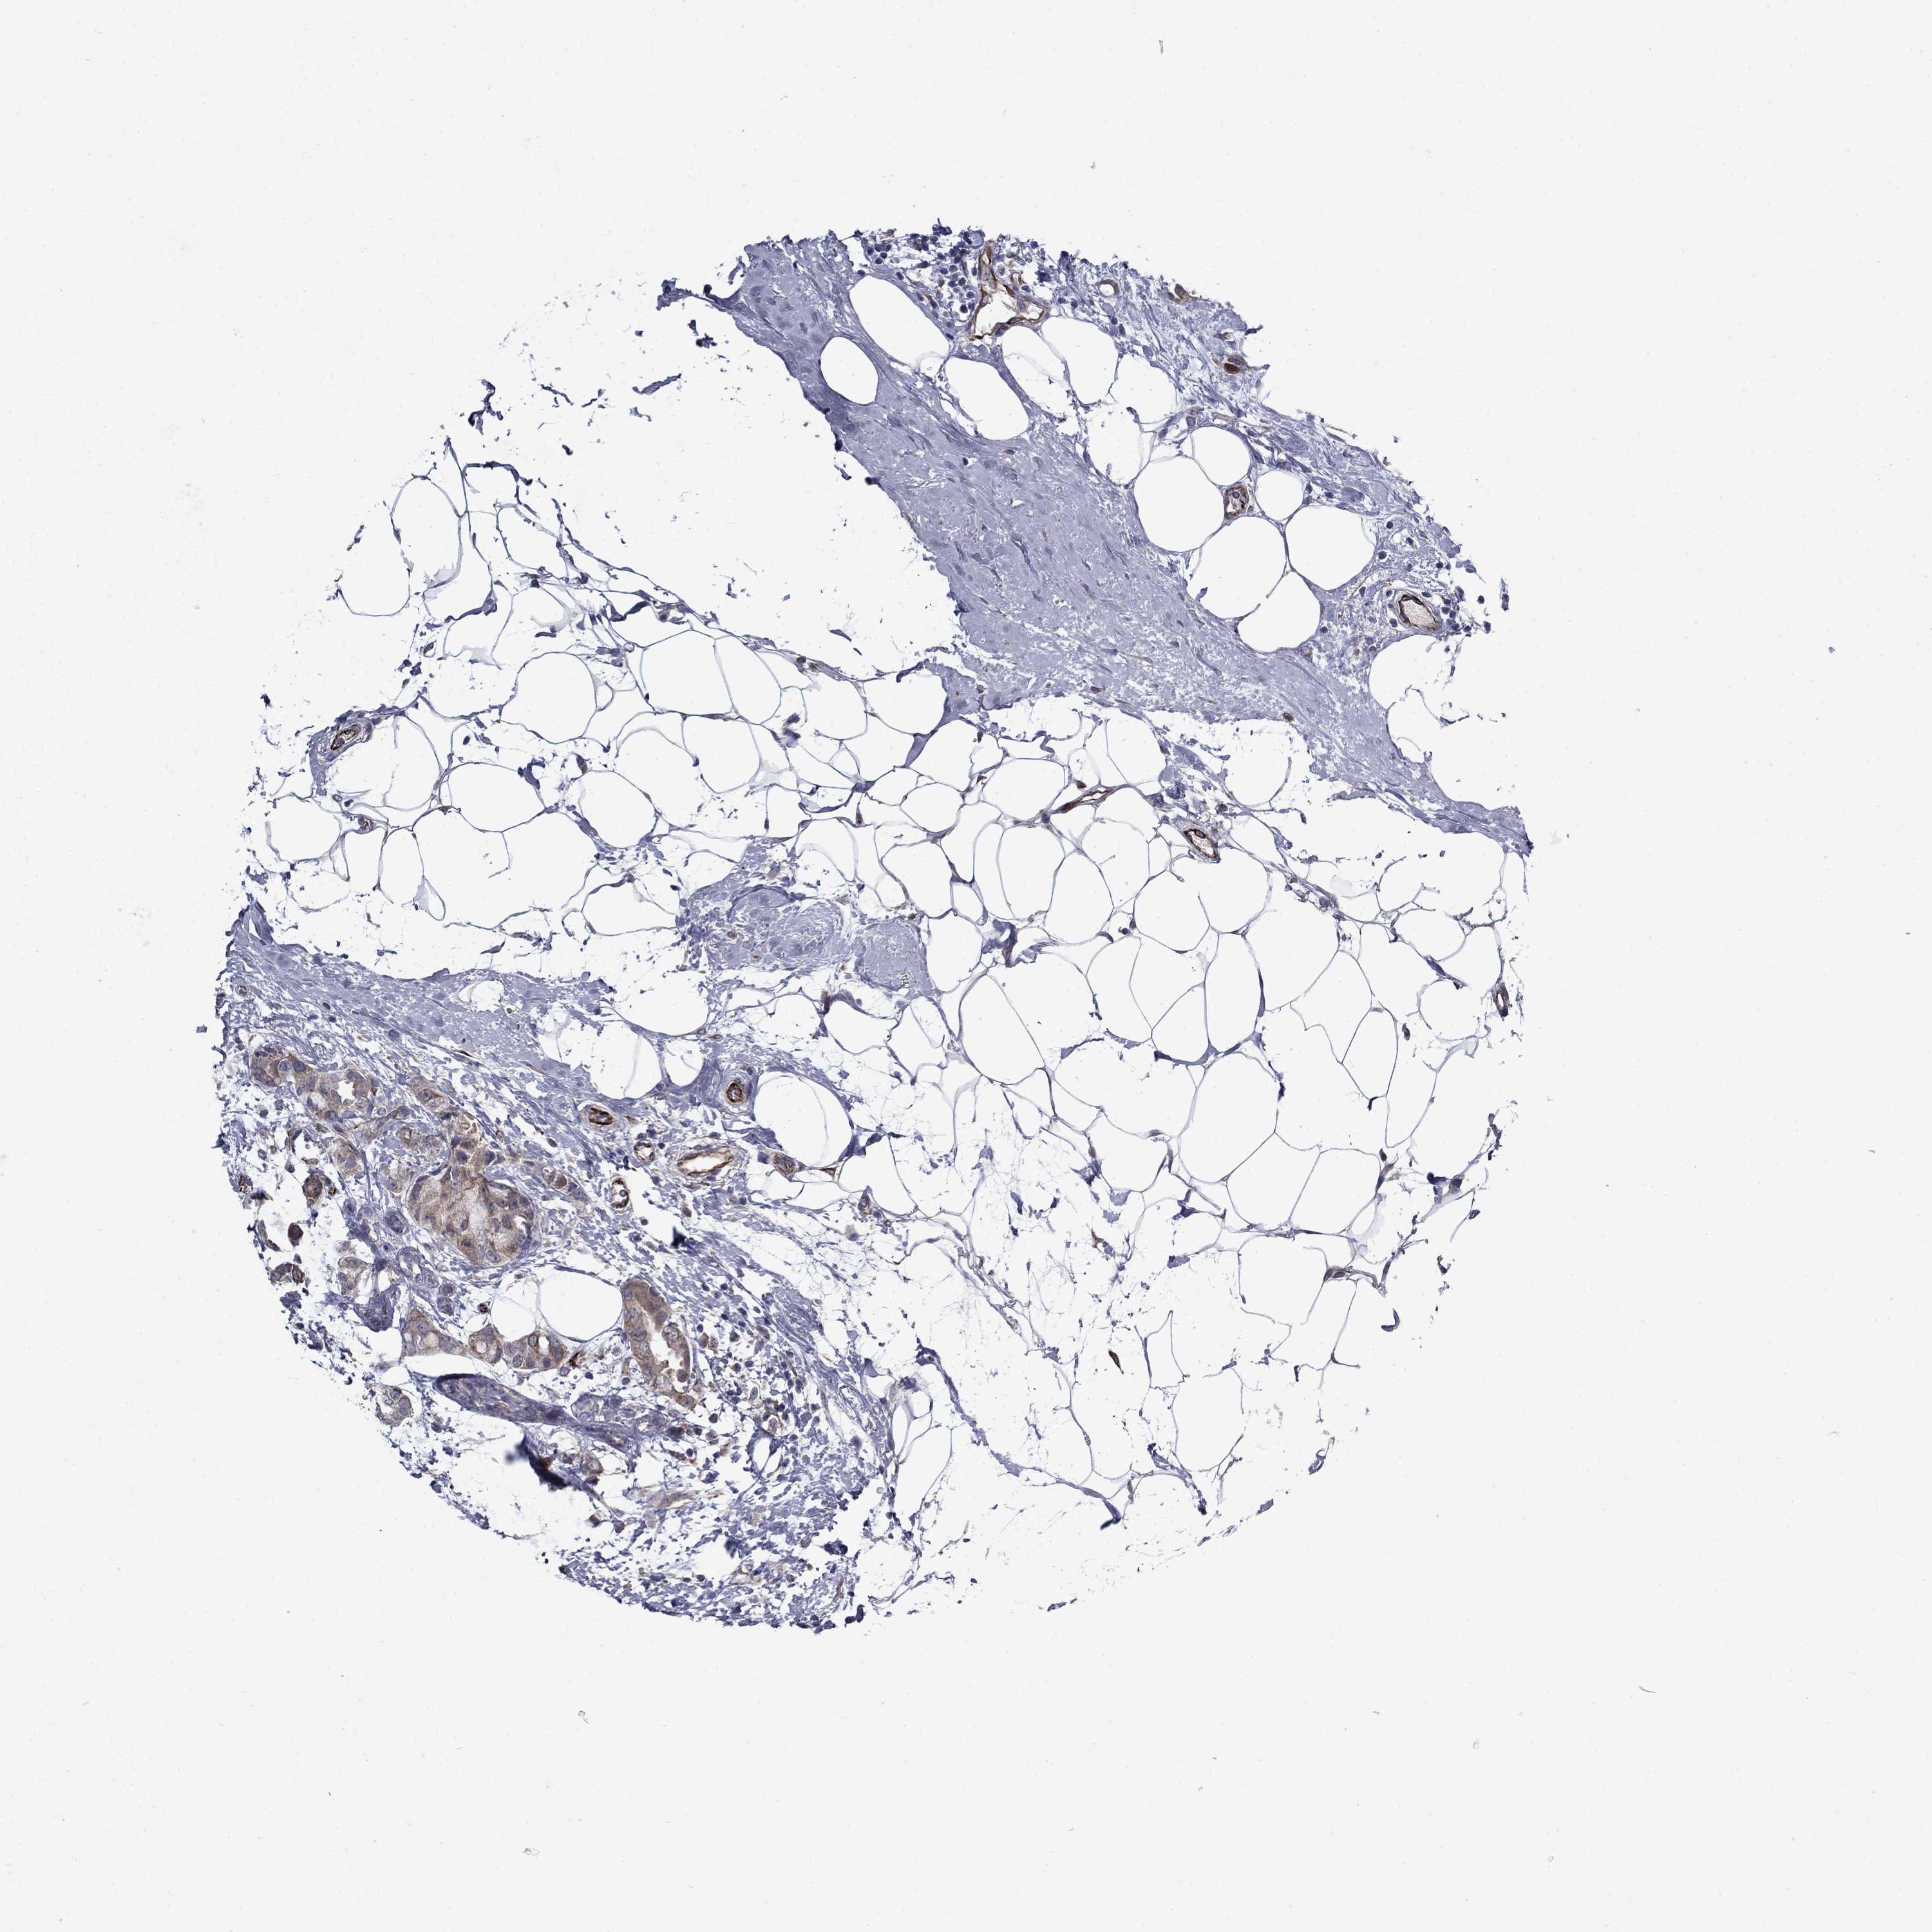

BRCA TCGA BRCA VALIDATION PROTEIN EXPRESSION